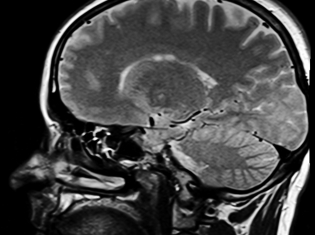

PML is a rare and serious brain infection caused by the John Cunningham (JC) virus. The JC virus is a common virus that is harmless in most people but can cause PML in some patients who have weakened immune systems.

BACKGROUND: Tecfidera is a drug used to treat relapsing forms of multiple sclerosis (MS), a brain and spinal cord disease in which patients experience multiple episodes of weakness, numbness, and other nervous system signs and symptoms that partially or completely resolve overs weeks or months. Patients may develop persistent symptoms and disability over time.